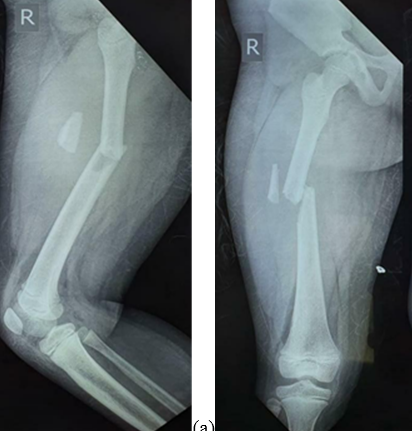

Figure 2: (a and b) Pre-operative anteroposterior and lateral radiographs.